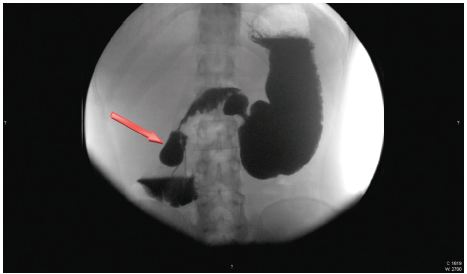

Face o resultado da TC, realiza trânsito gastro-duodenal onde se observa piloro permeável para o bolbo doudenal, que apresenta espessamento do relevo mucoso, aspeto este que se mantém em continuidade na primeira e segunda porções do duodeno, compatível com fenómenos inflamatórios. Observa-se, ainda, imagem aditiva com sinal «windsock» na 2a porção duodenal com 3,2 cm de diâmetro compatível com DDI (fig. 2) e dilatação de DII e DIII com cerca de 5,5 cm de calibre, com manutenção do relevo mucoso e conservação da distensibilidade, cuja causa localiza-se na linha média e é sugestiva de pinça aórtico-mesentérica. Efetua, também, endoscopia digestiva alta (EDA) que identifica algumas pequenas erosões agudas no antro gástrico, bulbite erosiva marcada e edema das pregas em DII condicionando estenose relativa com alguns restos alimentares impactados. Efetuadas biópsias apenas no bolbo e DII, revelando, no estudo morfológico, infiltrado inflamatório moderado da lâmina própria, constituído predominantemente por eosinófilos (cerca de 35 por CGA) sugestivo de duodenite eosinofílica (fig. 3).

Figura 2 Trânsito gastro-duodenal revelando imagem aditiva com 3,2 cm de diâmetro e sinal «windsock» em relação com divertículo intraluminal. A seta mostra o DDI.